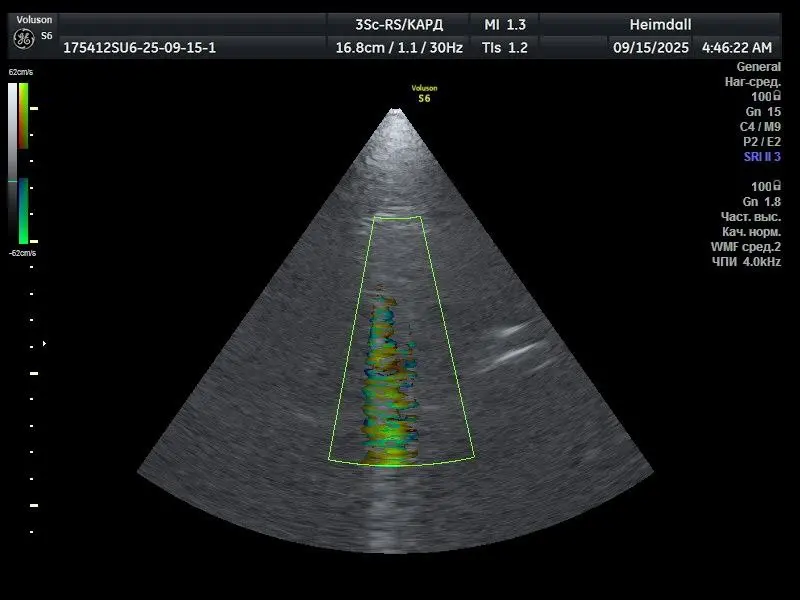

GE 3Sc-RS — фазированный кардиологический ультразвуковой датчик, предназначенный для визуализации сердца и сосудов. Обеспечивает работу в режимах 2D, цветового допплера (C) и импульсно-волнового допплера (PW). Высокая плотность элементов матрицы и фазированная технология требуют стабильной работы всех пьезоэлементов и модулей обработки сигнала. Проблема Пользователь сообщил о полной неработоспособности режимов C и PW. Во всех режимах наблюдались […]